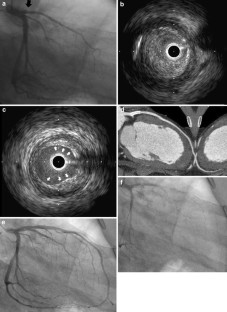

Fig. 1

Fig. 2